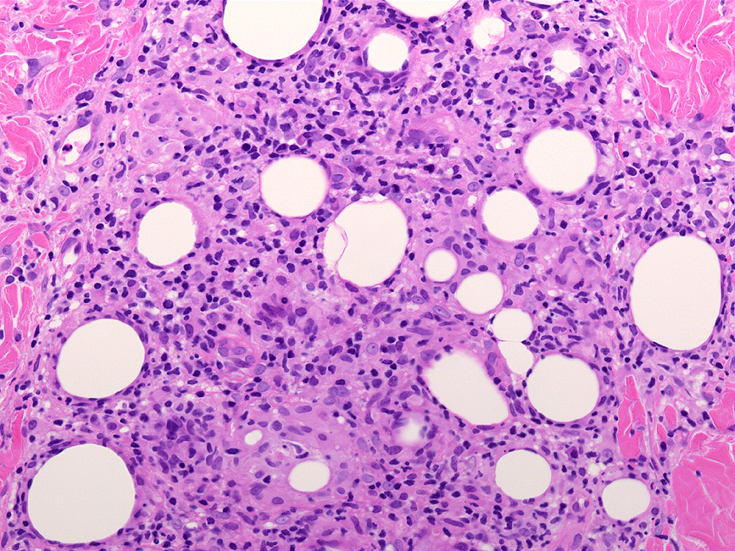

皮膚生検組織 サムネイルをクリックすると大きな画像がみられます。

組織所見*16*17*18

皮下組織に優位な, 小~中型 Tリンパ球の密な浸潤が特徴。ときに大型リンパ球や組織球が混在する。 リンパ球の異型は, わずかなものから明瞭な異型を示す症例までさまざまである。